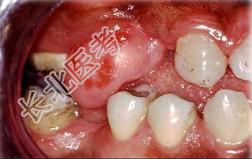

单项选择题组图为口内纤维瘤的外观,关于此病的描述不正确的是 ( )